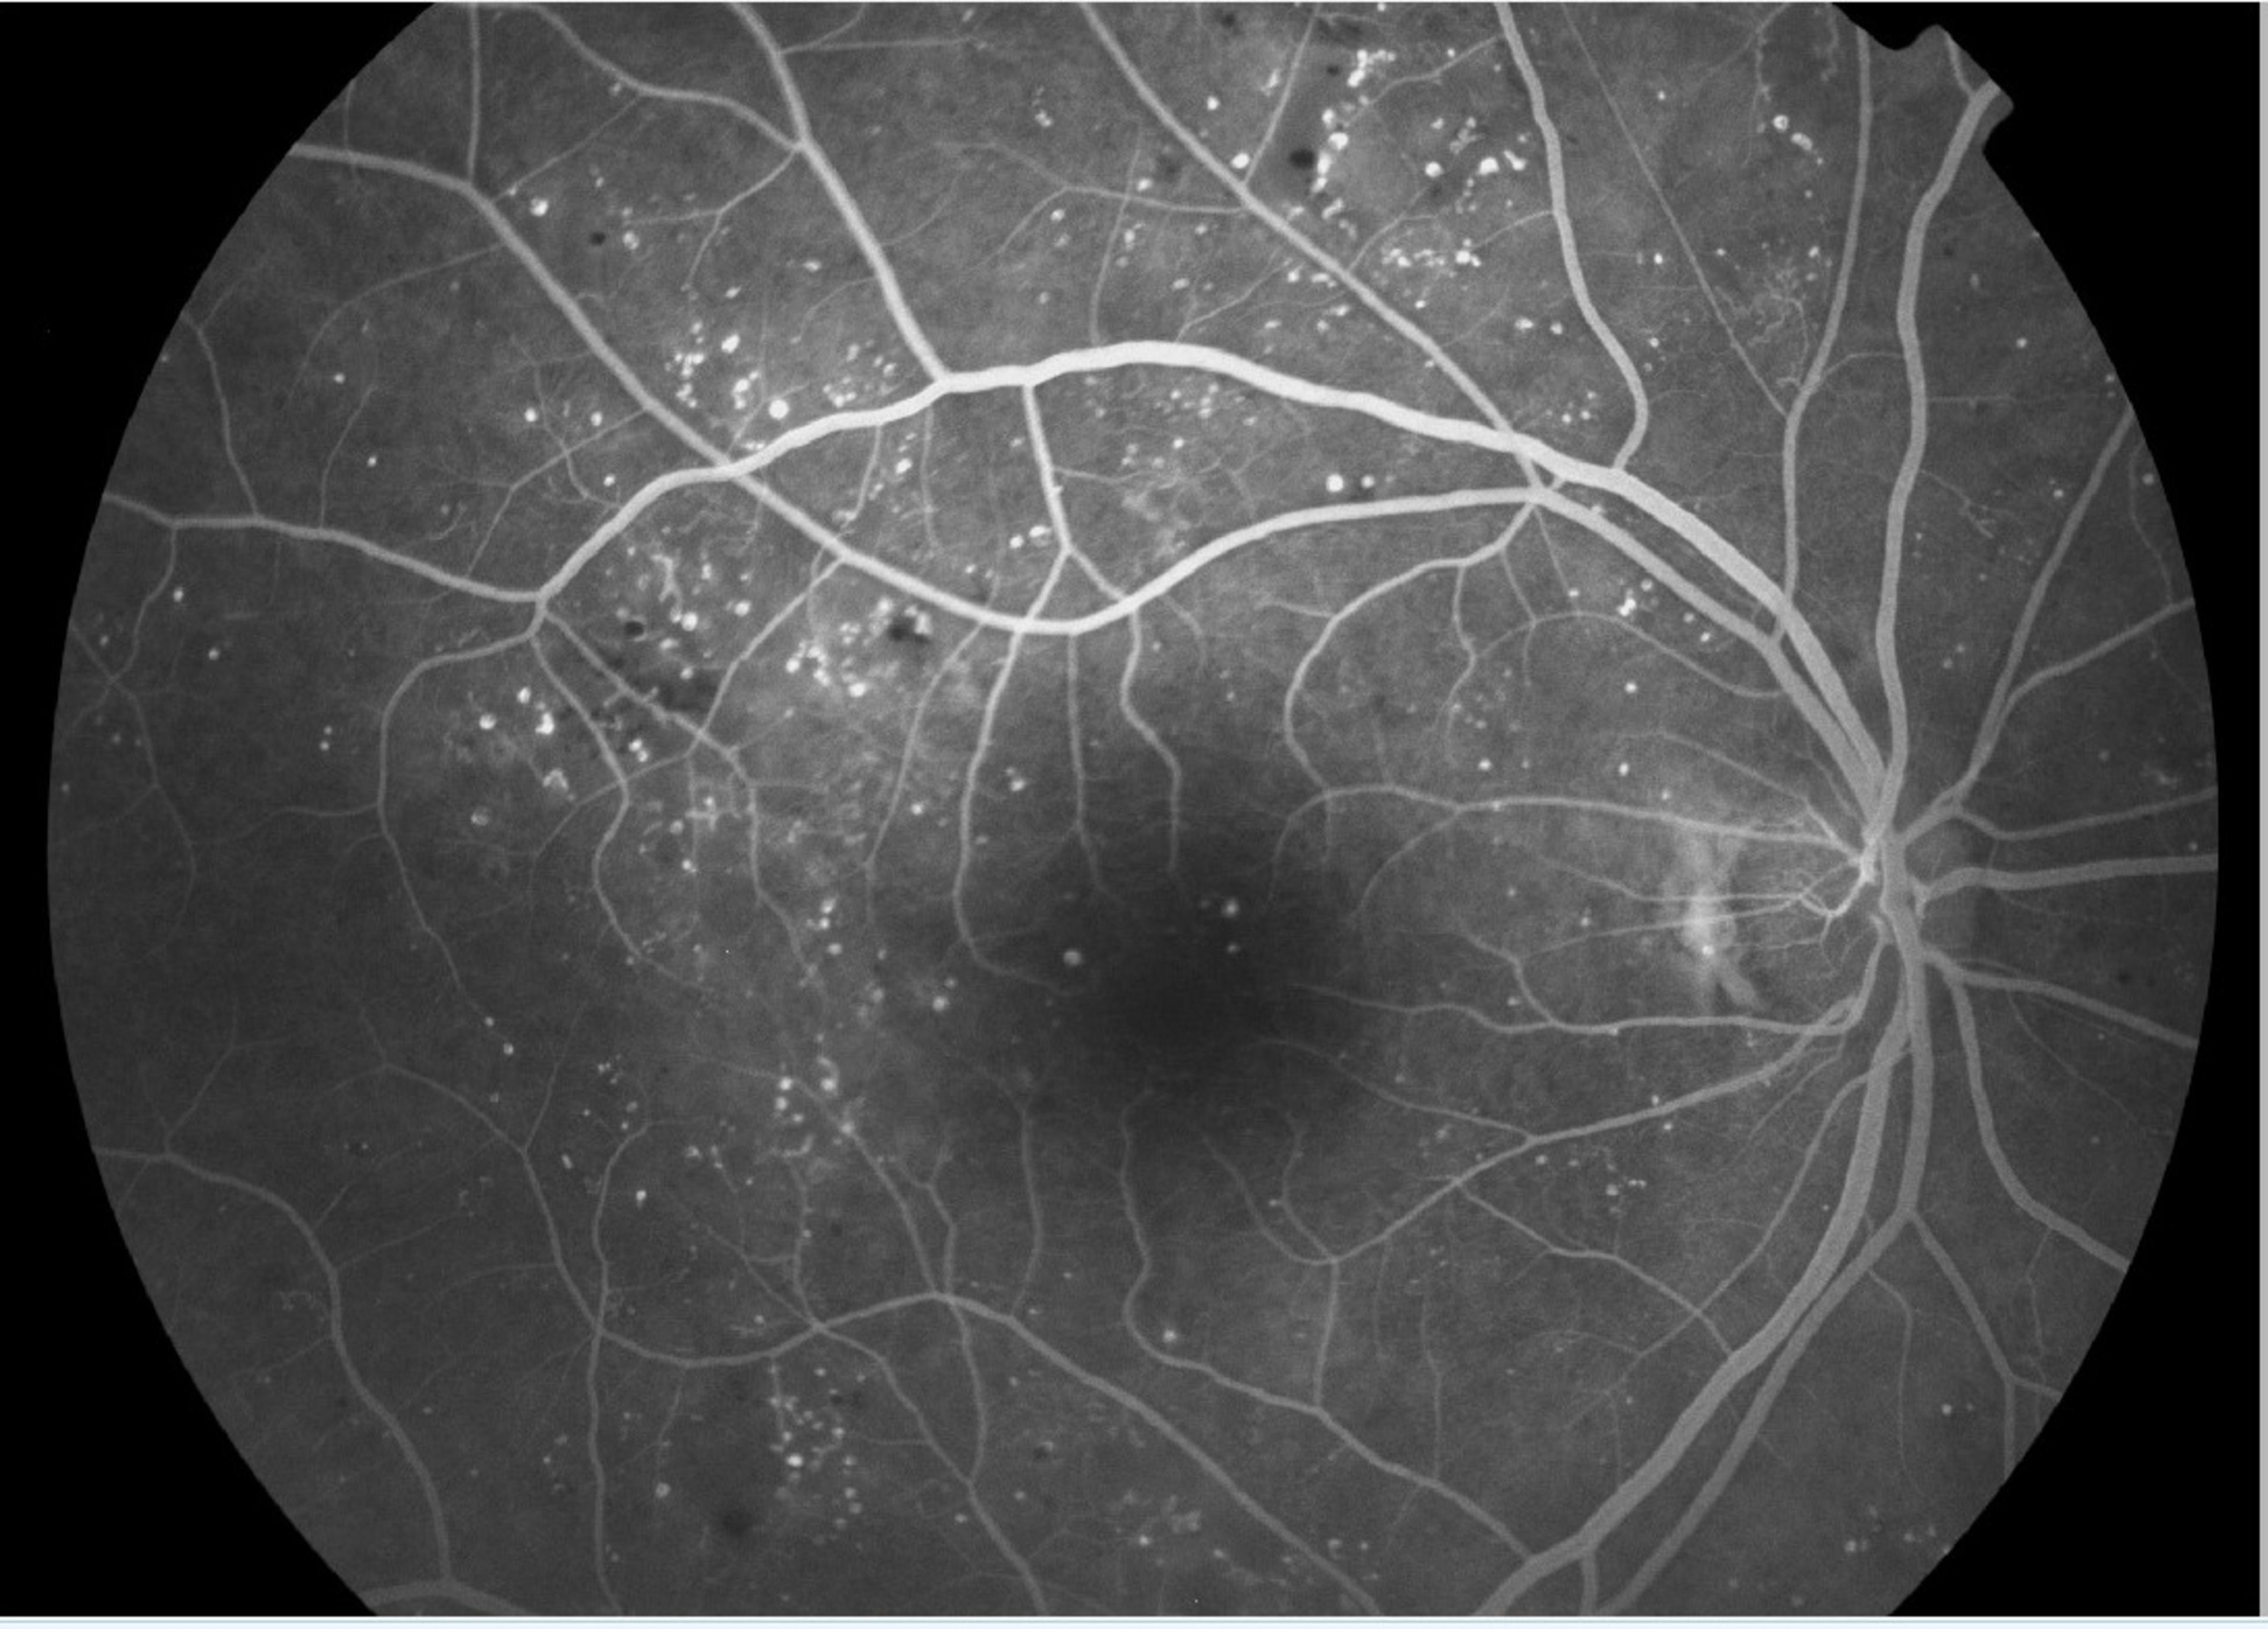

Silmän väriainekuvauksissa (FAG eli fluoreskeiiniangiografia ja ICG eli indosyaniiniangiografia) selvitetään verisuonten rakenteita ja toimintaa. Väriainekuvauksessa potilaan käsivarteen laitettavan kanyylin avulla ruiskutetaan väriainetta verisuonistoon. Väri kulkeutuu verenkierron mukana silmänpohjan pieniinkin verisuoniin, jotka eivät välttämättä näy kliinisessä tutkimuksessa. Tutkimuksen aikana silmänpohjista otetaan runsaasti valokuvia.